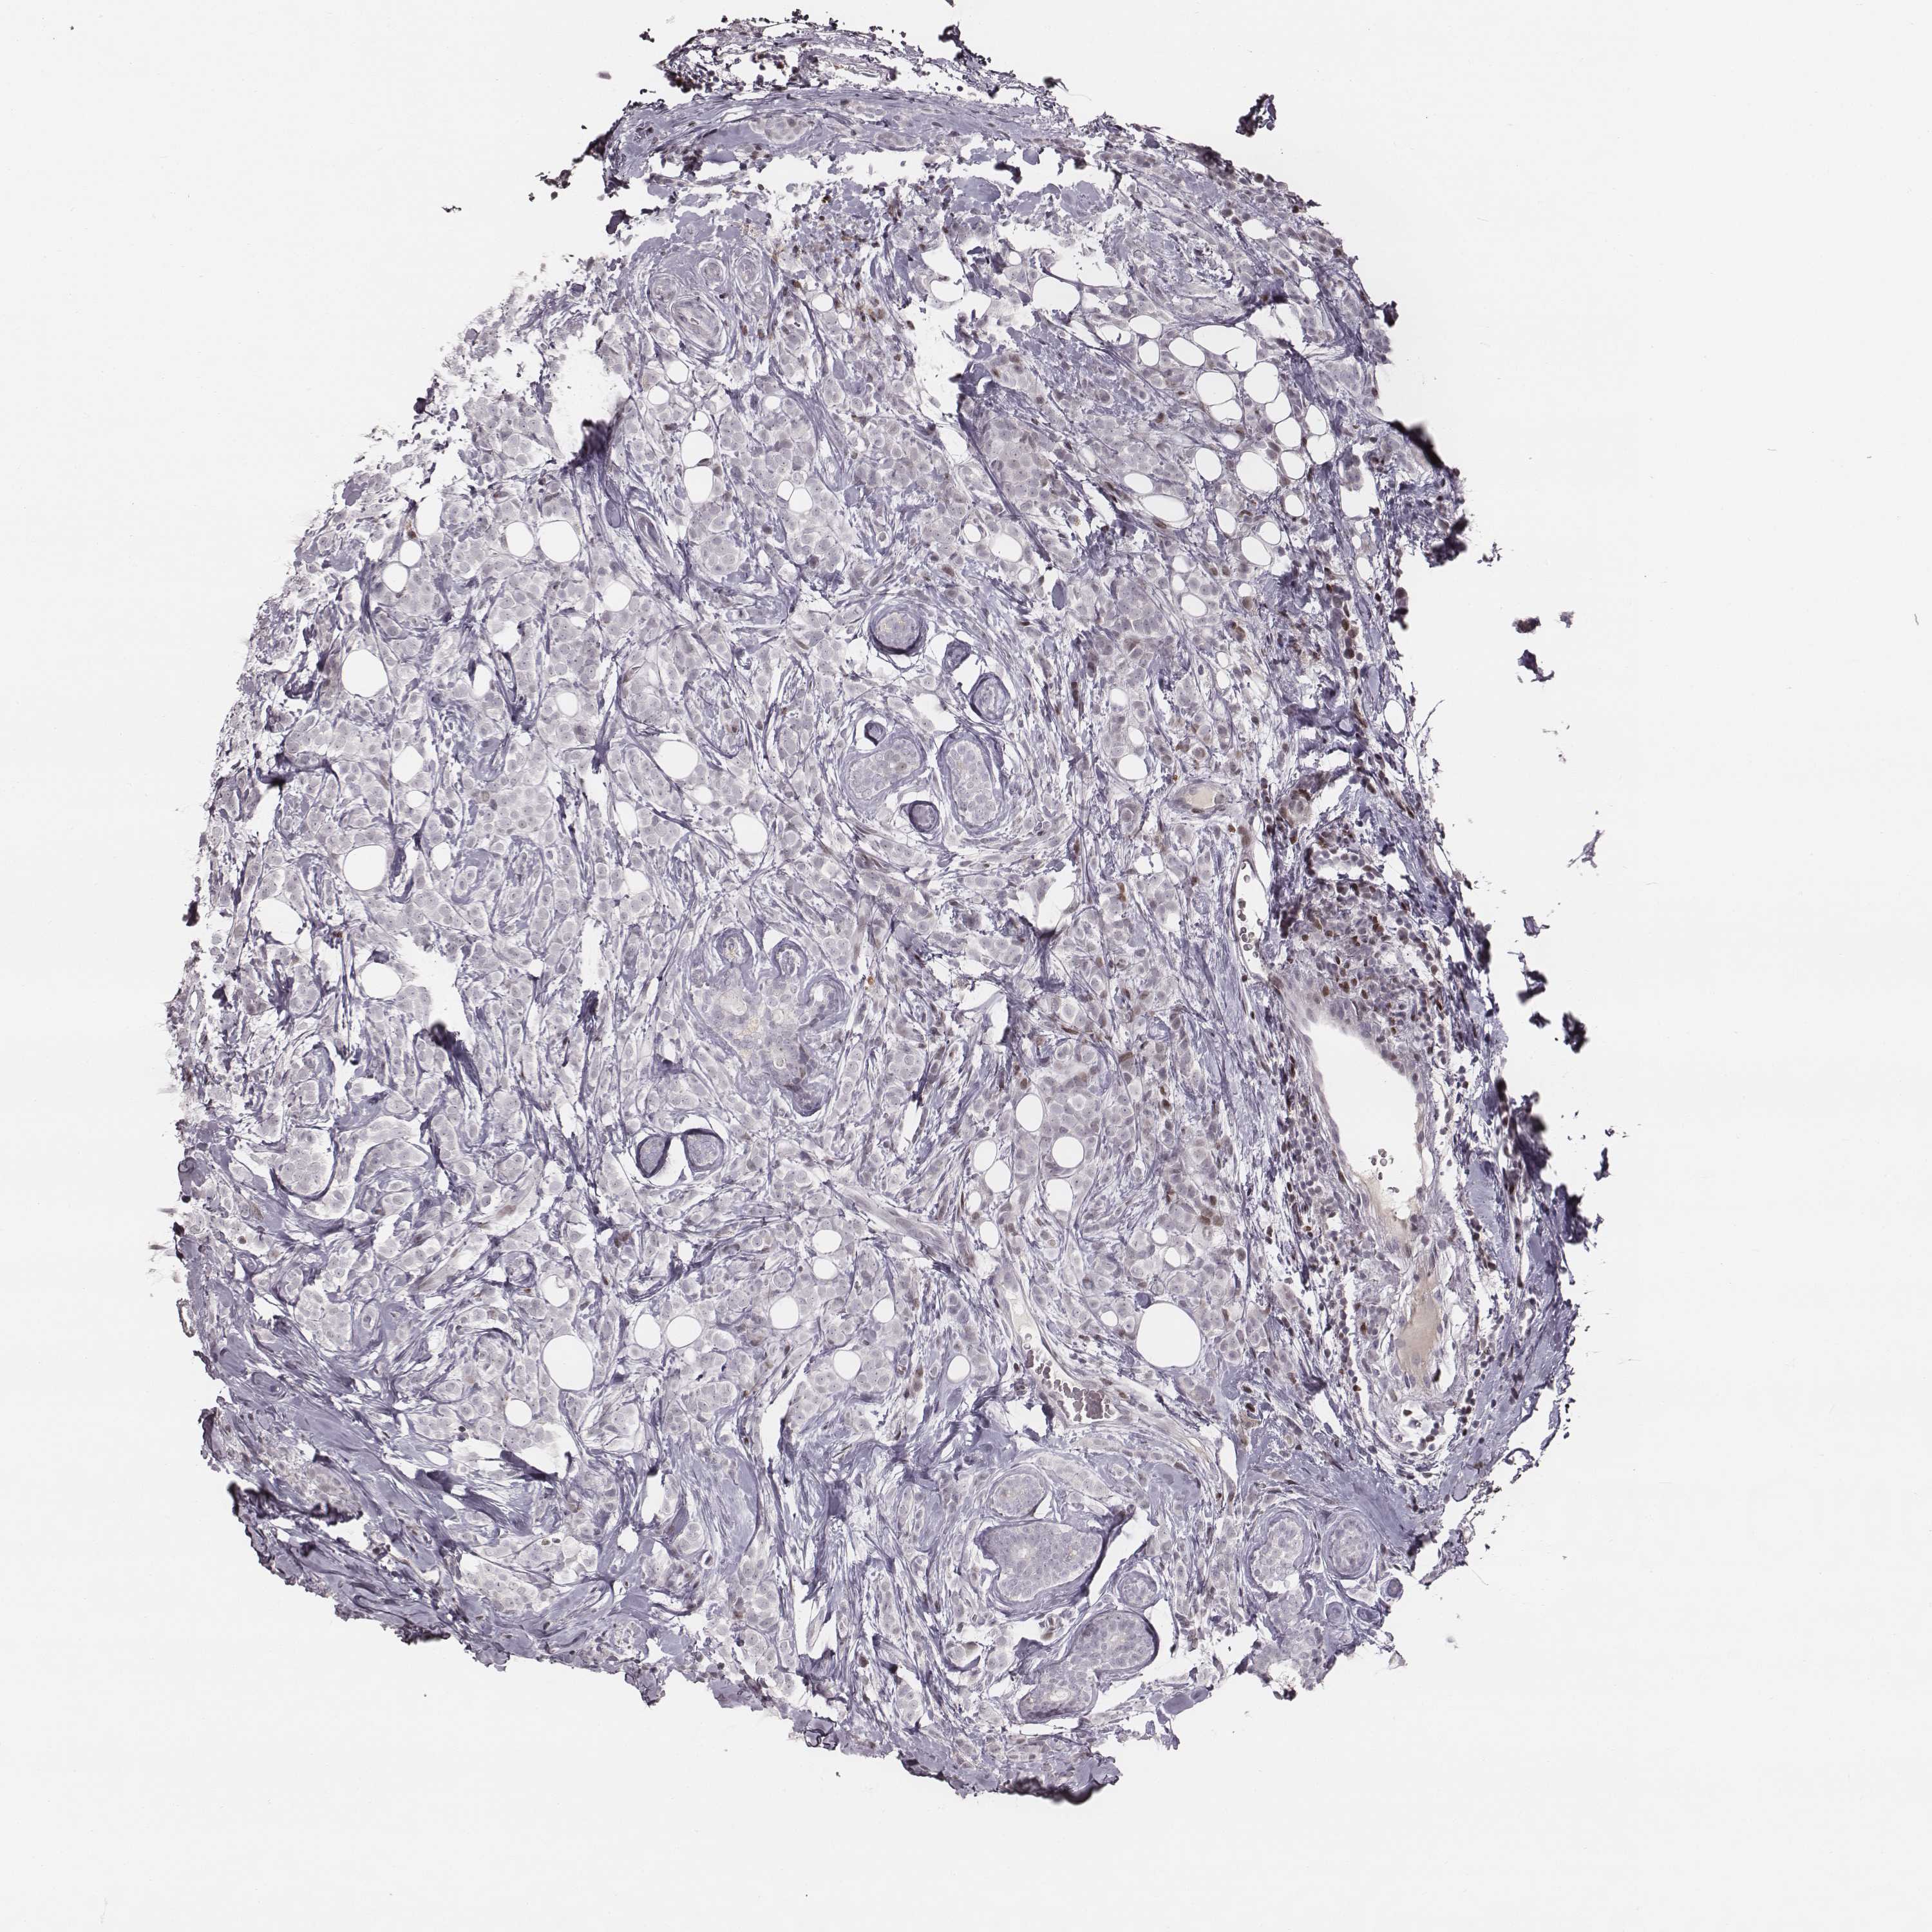

Breast cancer

Human cancer

CANCER BREAST CANCER Show tissue menu